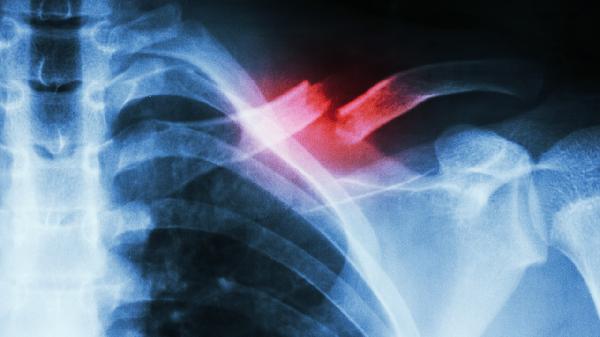

跌打损伤导致的疼痛可通过冷热敷、药物缓解和适度活动改善,严重时需就医。常见原因包括软组织挫伤、关节错位或骨折,正确处理能加速恢复。

正确处理跌打损伤需观察疼痛变化,持续加重或出现肢体畸形立即就诊。恢复期间保持损伤部位高于心脏水平,睡眠时用枕头垫高患肢。记录每日肿胀程度和关节活动度,2周未改善需影像学检查排除骨裂。日常运动前做好热身,佩戴护具可降低损伤风险,中老年人群注意钙质补充预防病理性骨折。